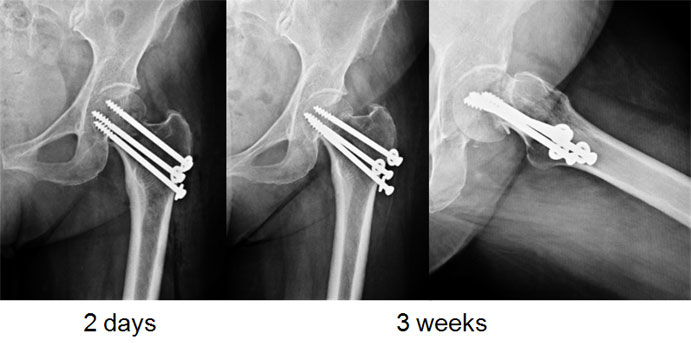

This 54 year old lady, smoker, had a slip and fell on her hip. There was a fracture of the neck of femur on the left side. The options in such a situation are to either fix the fracture or replace the joint either half (Hemiarthroplasty-only the ball of the joint is replaced) or complete (Total Hip Replacement-boththe ball & socket are replaced).

Since the hip joint was normal before the fracture, it was decided (with patient’s consultation) to do a fixation and try and salvage the hip. A closed reduction and percutaneus cancellous screw fixation (minimally invasive) was done.

The fracture seemed to be well on its way to heal. She was walking well though still with the walker.